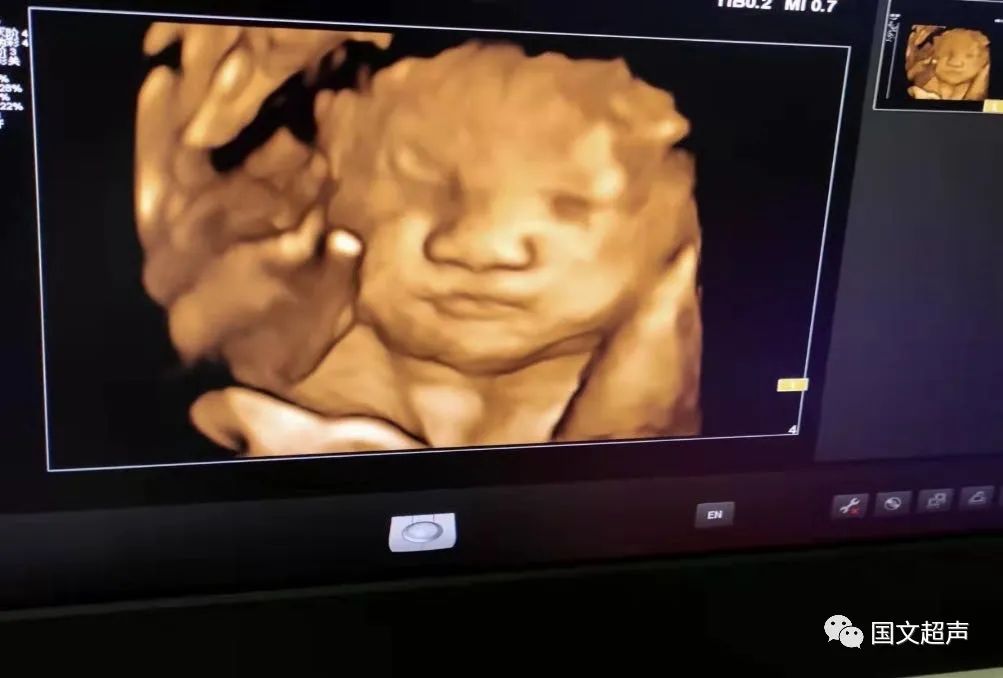

一.飛利浦EPIQ7高端四維彩超

我院目前使用的是飛利浦EPIQ7高端四維彩超,它擁有高品質(zhì)自動(dòng)成像分析技術(shù),分辨率及清晰度高,可以較清晰的顯示宮內(nèi)胎兒的生長(zhǎng)發(fā)育情況,為診斷胎兒先天性畸形,如唇裂、脊柱裂、顱腦發(fā)育異常、骨骼發(fā)育異常、心血管畸形等提供準(zhǔn)確的科學(xué)依據(jù)。